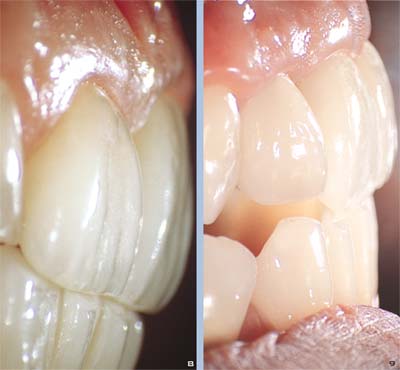

Abb. 4 und 5 Klinischer Fall vor und nach der Versorgung, dem Ersatz einer ästhetisch unbefriedigenden Restauration. Wie man in Abbildung 8 sieht, war die Kronenform das primäre Problem. Die zentralen Schneidezahnkronen weisen ein Verhältnis von Länge zu Breite von 1:1 auf, was die quadratische Zahnform ergibt. Besser wäre ein Verhältnis von 0.75:0.80, dies ergibt eine ästhetisch gefälligere Form2-4. Die mangelhafte Passgenauigkeit im Randbereich, die zu einer gingivalen Rezession an allen Schneidezähnen geführt hat, ist sichtbar. Die neuen Kronen zeigen die richtige Kronenform und -länge. Die natürliche Erscheinung der Kronen resultiert aus der Verlagerung des Zenits des Gingivaverlaufs nach distal unter Beachtung der zentralen Zahnachse.

Abb. 6 Seitliche Ansicht der Kronen durch das OPMI 1 Mikroskop (Zeiss) mit integriertem Ringblitz. In dieser 25fachen Vergrößerung erkennt man deutlich die Unvollkommenheit der Randadaptation und das Ausmaß der Gingivaretraktion.

Abb. 7 25fache Vergrößerung der neuen Versorgung (Feldspat-Keramikkronen) sechs Monate nach Einsetzen.

Abb. 8 und 9 Gleicher Fall wie in den Abbildungen 4 bis 7, bei stärkerer Vergrößerung im OP-Mikroskop: klinische Situation sechs Monate nach dem Einsetzen. Perfekte ästhetische Integration in Relation zu den Unterkieferzähnen. Vor allem die Ränder zeigen ein korrektes Austrittsprofil und eine ausgezeichnete Beziehung zum Weichgewebe.